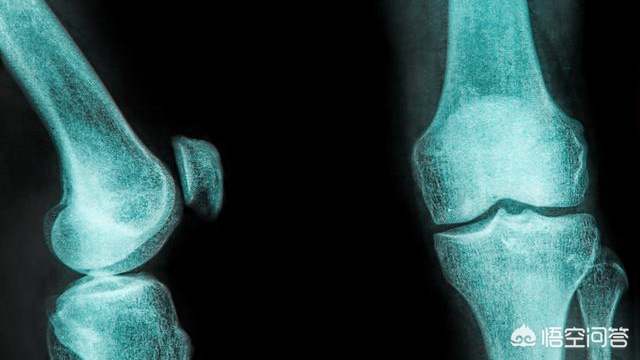

我们需要先了解清楚髌股关节处的软骨在我们的人体中起到什么样的作用。其实髌股关节就是我们膝关节的一部分,而髌股关节处的软骨,在我们的关节活动中是有很好的保护作用的,它主要的功能是缓解外力对关节处的压力,在这个过程中,软骨会在压力的作用下被压缩,而当压力消失时软骨又可以伸展回原状,保护关节处的骨骼不会被磨损伤害,充当着弹性垫的作用。

髌骨和股骨共同构成了髌骨关节,而软骨就附着在髌股关节中,这种附着结构能够有效的减少运动给关节带来的损伤,它可以使关节处的活动更加地流畅和缓冲压力等。也正因软骨这种“牺牲小我,完成大我”的精神,使得髌股处的软骨自身更容易受到伤害,一般软骨是没有或者是只有很少一部分的血液供应的,当软骨细胞的排列因为受到损伤被打乱和被破坏时,愈合状况是很不理想的。